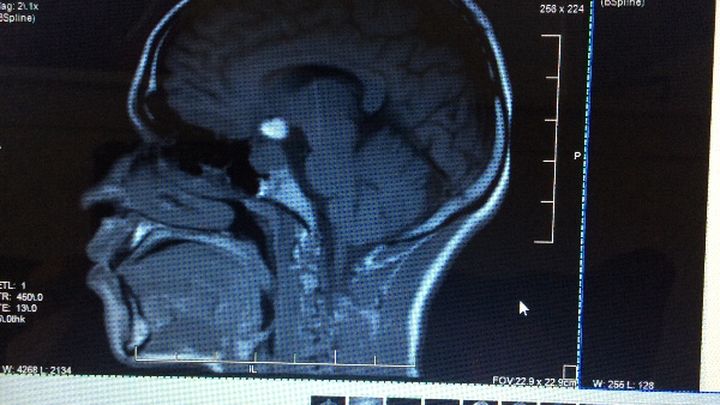

Before being diagnosed with a Pituitary Tumor, Luis was going to college at Florida Technical College, and used to play basketball at St.Cloud High School. Luis and his family need help from friends, family, and anyone else who would like to donate money towards medical treatment, medications, transportation, and for medical bills. Luis has already turned 21 years old, therfore, he no longer has medical insurance to contribute towards these items. He most take the medication in order to make the tumor shrink, to have surgery to remove the tumor. Also, luis is now having seizures and needs medications for it as well. For this reason we have set the goal for the amount of money we want to raise high, but any amount donated will be greatly appreciated.

Antes de haberme diagnosticado con un Tumor Pituitaria era un joven normal que cursaba enel Florida Technical College , antes en la escuela Superio de St Cloud jugaba enel equipo de Baloncesto. Necesitamos su ayuda para la deuda ya de 500,000 en hospitales y para medicamentos, medicos, transportacion, ect. Ya que cumpli 21 años no tengo seguro medico. Les agradezco su ayuda anticipadas de todo corazon.